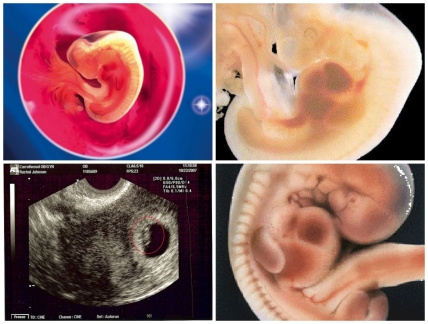

Сейчас ребенок еще совсем крошечный, чуть больше гречневого зернышка, его вес около 3 грамм и длина 4-6 мм., и хотя он изогнут в виде буквы С, уже можно увидеть, где будут его головка, спинка, ножки. На пятой неделе у него начинается формирование половой системы, верхних дыхательных путей, печени и поджелудочной железы.

Именно на сроке в 5 недель у малыша частично закрывается нервная трубка, полным ходом идет развитие нервной системы ребенка, спинного и головного мозга, также формируется кровеносная система. Сейчас, как, впрочем, и ранее, будущей маме важно принимать фолиевую кислоту, чтобы все эти органы и системы жизнедеятельности малыша сформировались без пороков и дефектов.

Если тест на беременность показал положительный результат, вы можете пройти УЗИ для подтверждения этого события и оценки развития беременности. На 5 неделе беременности УЗИ покажет, где плод закрепился в матке, не является ли беременность внематочной. Также в некоторых случаях на 5 неделе беременности с помощью УЗИ уже можно увидеть, как бьётся сердце малыша.